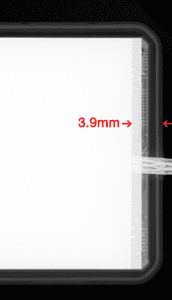

For historical reasons, most sensors place necessary electronics near the edge where the cord exits the sensor. The result is a dead space of up to 6mm, since the electronics cannot also be part of a sensor’s active imaging area. So, for bitewing purposes, the very edge used to capture the canine/premolar contact may not capture any image at all for its first 3-6mm. Clinicians who regularly place sensors instantly see this as a problem.

Figures 2a through 2d demonstrate how XDR’s imaging area extends further toward the sensor’s mesial edge. XDR has patented this approach under US #9357972B .